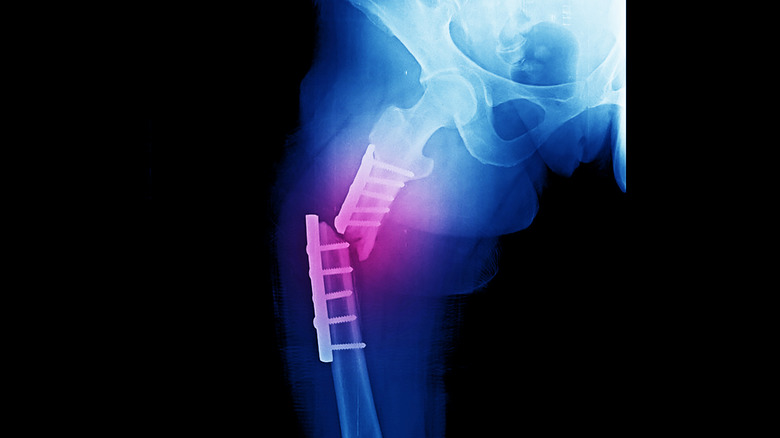

Sharing an X-ray of the injury via Instagram, Hawk describes the challenges that lie ahead in the recovery process, writing, "Yesterday sucked. I broke my elbow 20 years ago and managed to make a full comeback; this recovery for a broken femur will be much harder because of its severity (and my age)." Despite these obstacles, Hawk credits his good mental health to skating and is adamant about skating until he is no longer physically able to. With this mindset, Hawk writes, "A broken leg – with plenty of hardware – will probably be the biggest test of that creed. I'll be back... maybe not at full capacity but I resigned to that notion years ago as I approached 'mid-life.'"

Unlike other commonly broken bones such as the arm, the femur — connecting the hip and the knee — is the heaviest bone in the human body (via Cleveland Clinic). Because it would take an enormously large blow to break this strong bone, a broken femur is considered a severe medical injury requiring a long recovery process.

According to experts at the Cleveland Clinic, because the breakage can be severely painful, those with a broken femur struggle to place weight on the leg. Immediate surgical intervention is required within 48 hours or less after having incurred the injury, and additional treatment may involve using a leg splint to keep the bone in place. Pain management medication, in-home care, and ongoing physical therapy are also implemented throughout recovery — a process that can take up to 6 months post-surgery.